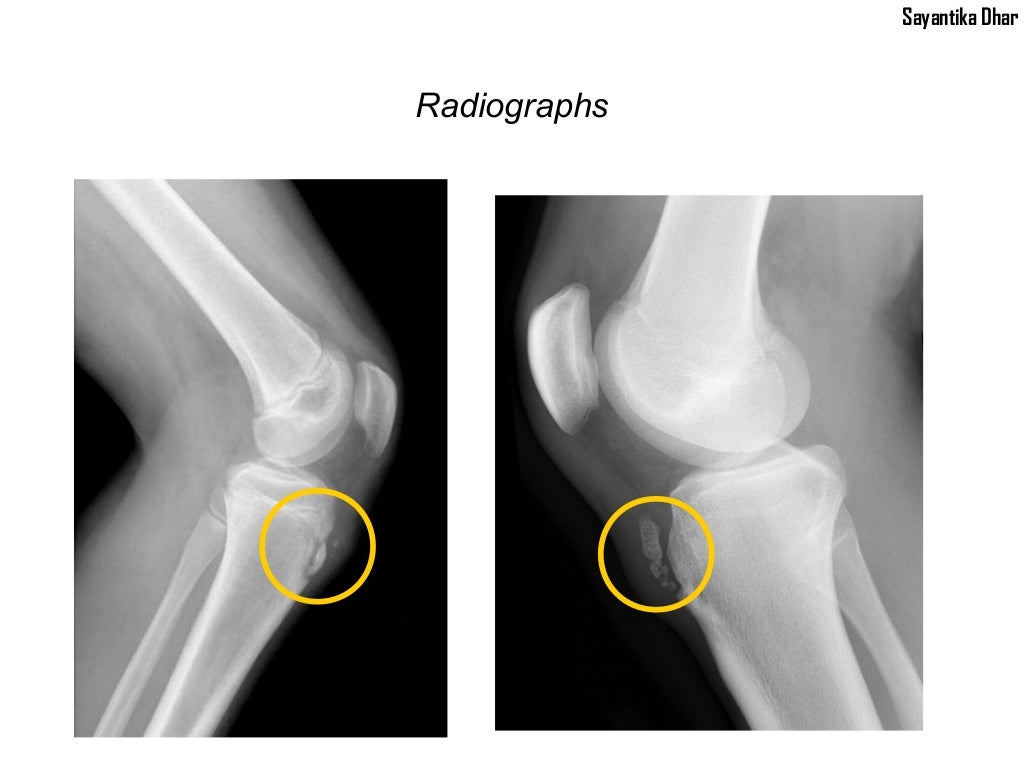

From www.slideshare.net

Osgood Schlatter Disease Osgood Schlatter Right Knee Icd 10 Icd 10 code for juvenile osteochondrosis of tibia tubercle. m92.523 is a billable diagnosis code used to specify juvenile osteochondrosis of tibia tubercle, bilateral. icd 10 code for juvenile osteochondrosis of proximal tibia. Apophysitis of tibial tubercle resulting from repeated. Anatomy of anterolateral aspect of right knee. Osgood Schlatter Right Knee Icd 10.